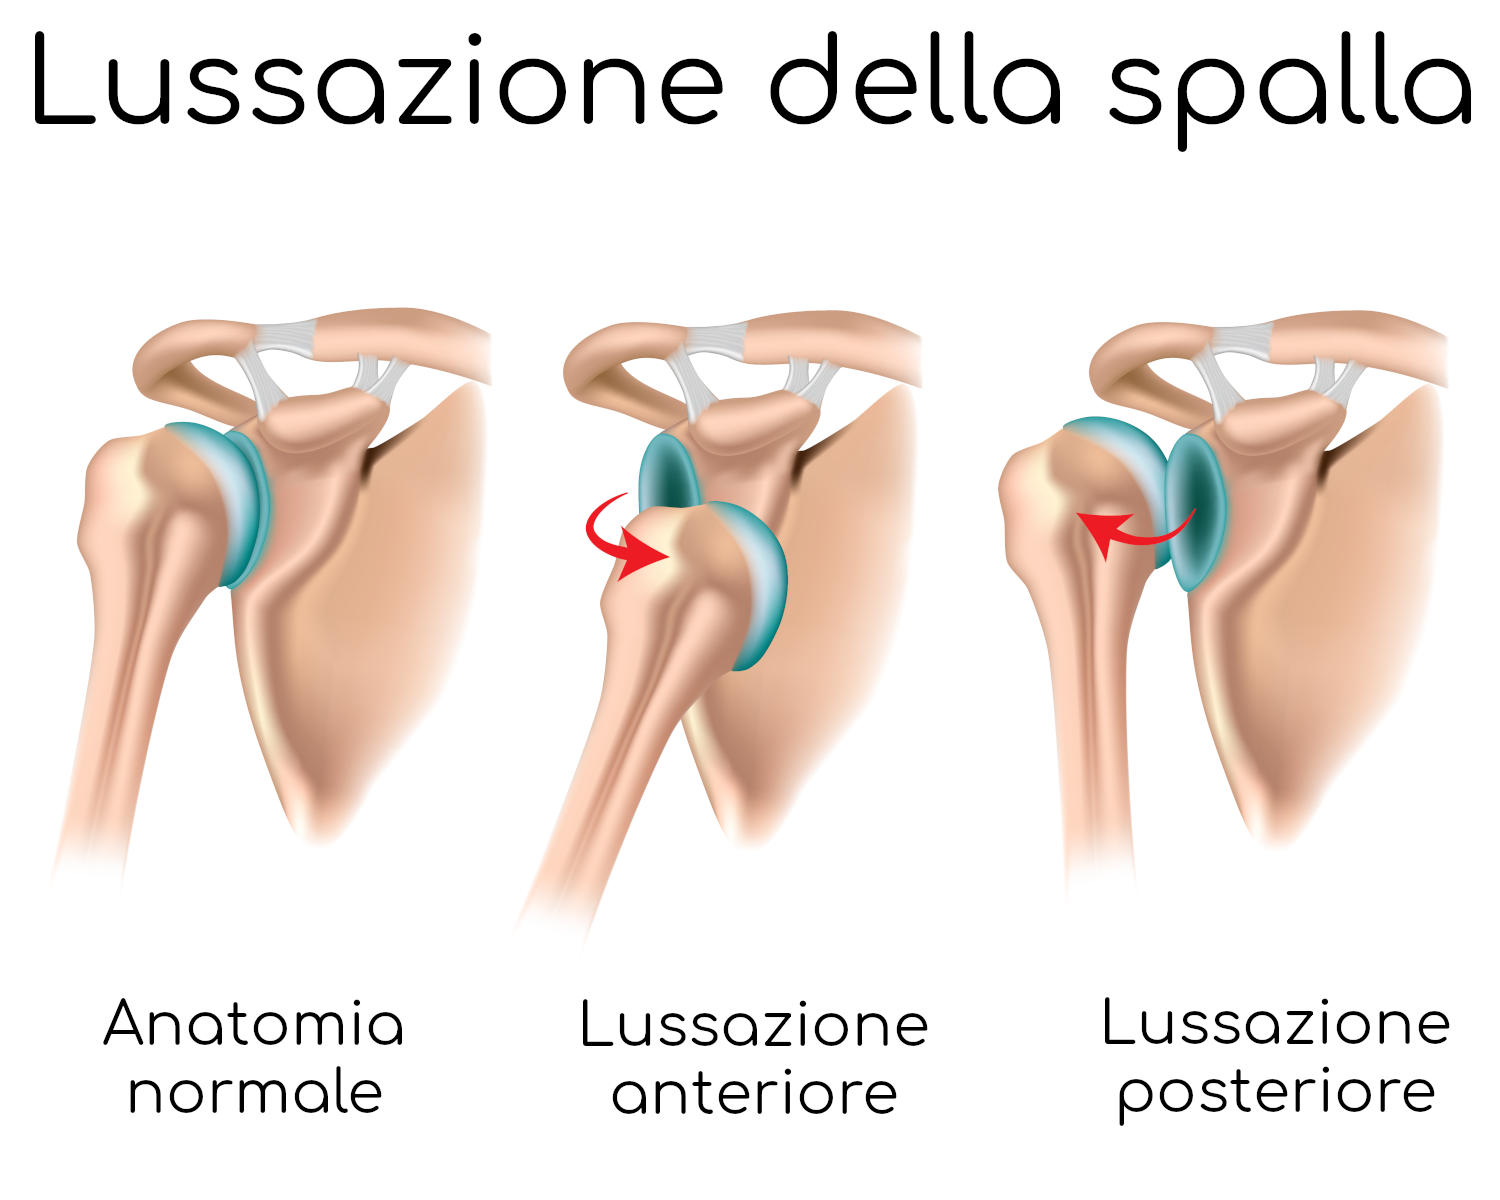

Una lussazione della spalla consiste nella fuoriuscita della testa dell’omero dalla cavità glenoidea della scapola, sua sede naturale (come si vede in figura).

La lussazione della spalla si classifica in diverse tipologie:

- Anteriore: quando la testa dell’omero lussata si sposta in avanti rispetto alla cavità glenoidea.

- Posteriore: rappresenta la tipologia più rara e più grave e si verifica quando la testa dell’omero si sposta posteriormente rispetto alla scapola

Tra tutte queste tipologie, la più frequente è rappresentata dalla forma parziale e anteriore che si presenta in quasi il 90% dei casi.